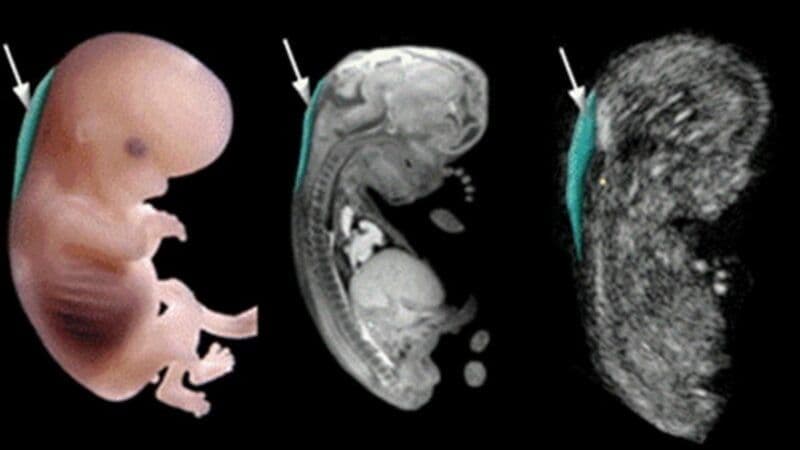

1. Độ dài xương mũi với tuần tuổi thai tương ứng

Độ dài xương mũi với tuần tuổi thai tương ứng có mối liên hệ chặt chẽ và tăng dần theo tuổi thai, vì vậy đây là chỉ số quan trọng khi đánh giá sự phát triển của thai nhi bằng siêu âm. Thực tế cho thấy, chiều dài xương mũi tăng gần như tuyến tính từ tam cá nguyệt giữa.